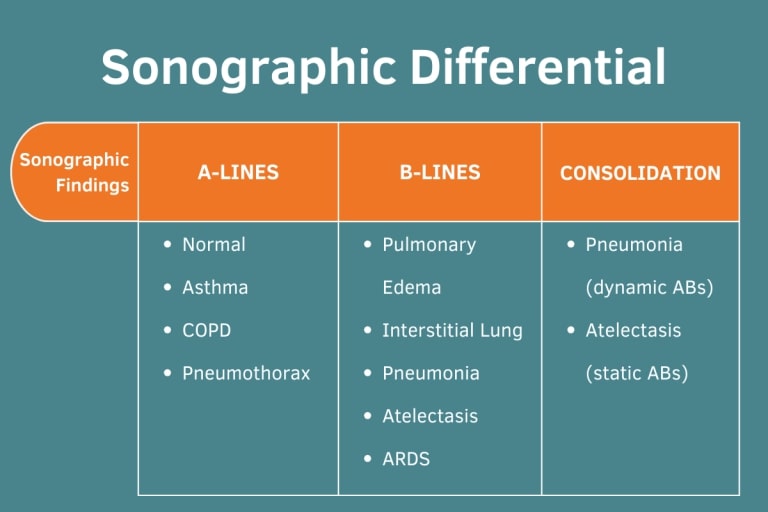

Learning the “ABCs” of the lung can be helpful for interpretation of sonographic findings.

“A” or A-lines can be regarded as a normal lung artifact, but can also be seen in pneumothorax, asthma exacerbation, and COPD exacerbations in the right clinical context.

“B” or B-lines can be seen in pneumonia, pulmonary edema, interstitial lung disease, atelectasis, and acute respiratory distress syndrome (ARDS).

“C” or Consolidations are commonly seen in pneumonia and atelectasis and can be distinguished by clinical context and presence of static vs. dynamic air bronchograms (ABs).

Check out the sonographic images.